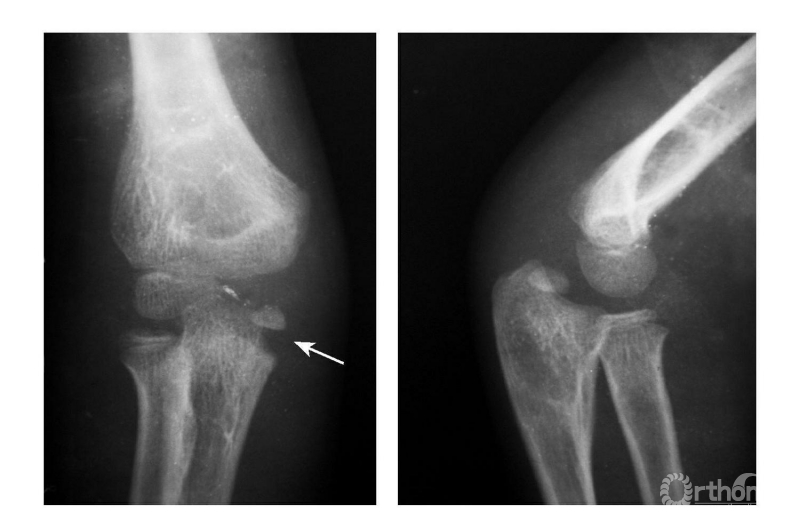

Ⅰ度损伤:

例:内上髁骨骺并带一皮质骨片略下移位(图3)

图3

Ⅱ度损伤:

例1:内上髁骨骺分离并带一模糊的骨皮质,并向外侧旋转,而达关节水平(图4)。

图4